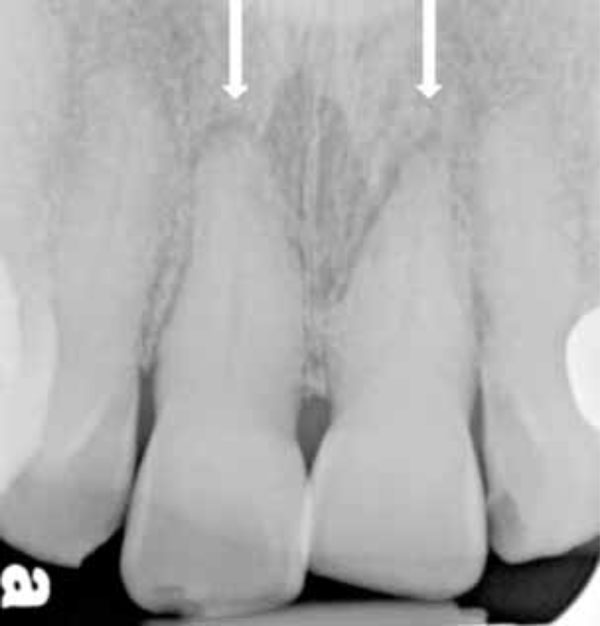

Initial periapical radiograph. Luxation of the incisors is apparent.

Pictures were taken to document her condition (Figs. 1-4, 6, 7). Alginate impressions of her upper and lower teeth were made to enable fabrication of diagnostic models. Radiographs were taken. The periapical radiographs (Fig. 5) showed a shadow around the roots of her front teeth, which indicated luxation injuries to the central incisors. She was able to make full bilateral contact with her posterior teeth, but her upper and lower incisors also made contact in centric occlusion, an unwelcome result of the fall. Previously, the patient never had anterior tooth-to-tooth contact - her pre-injury occlusion was a Class II malocclusion with a large overjet (approximately 5 mm) - so this altered bite condition bothered her. Bruises to her face and lips were also noted.